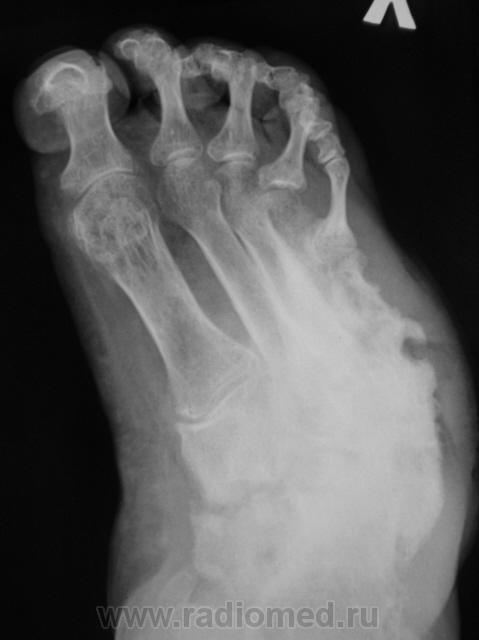

Пациентка направлена на рентгенографию стоп.

Направительный диагноз - "Диабетическая ангиопатия".

Хирург, увидев только одну стопу - правую, левая, еще была в работе, ответственно заявил - "остеогенная саркома"...

посмотреть бы в "стёклах", пока склоняюсь к остеобластокластоме..

Системное поражение, возможно как следствие диабетической ангиопатии;слева V плюсневая кость с прерывистым контуром ( возможно остеонекроз на фоне ангиопатии). Не видел подобного ранее.

Картинка вобрала в себя все, что клинически называют "диабетическая стопа". Здесь последствия и ангиопатии, и нейропатии, и присоединившейся инфекции. По-моему, имеется и трофическая язва. Прямо студенческий случай. Хотя, я тоже ранее таких стоп не видел.

Было бы односторонне поражение, подумал бы про мелореостоз.

Хронология с 1997 года.

Так все-таки, изменения в 5 плюсневых первично-диабетичны (такого не описывают в учебниках), или per contuitatem от язв?